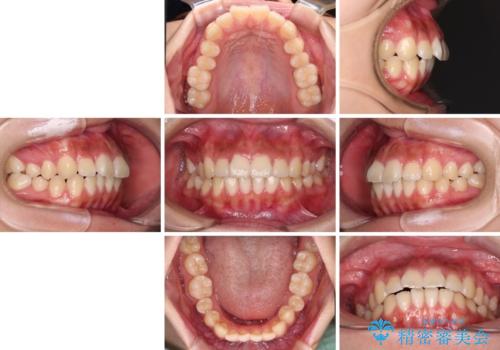

- 口元から飛び出てしまう前歯を気にして来院された患者様です。

上下前歯が嘴のように前方に突出しており、唇が閉じにくい状態であったため、上下左右の第一小臼歯4本を抜歯して、口元の突出感を改善することとしました。

目立たない装置を希望とのことで、上顎が裏側、下顎が表側のハーフリンガル装置を用いることとしました。